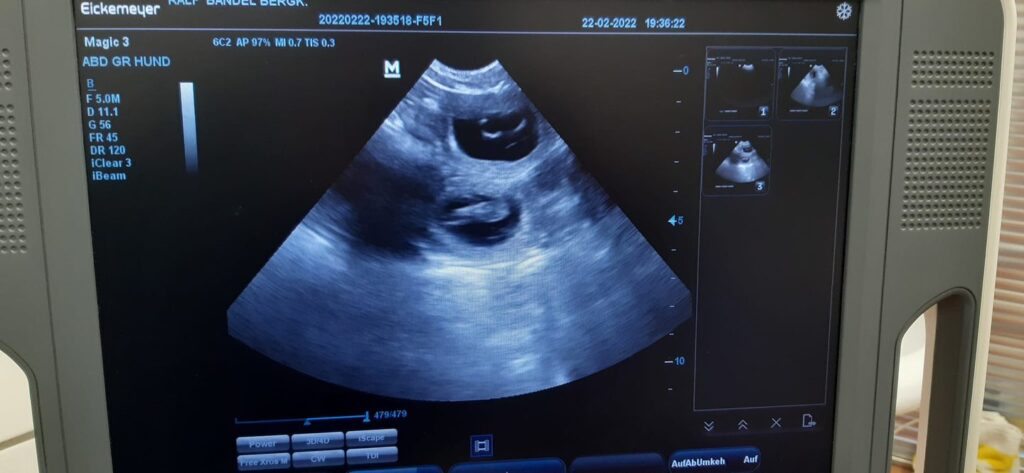

22.02.2022

Full House

Meine Vermutung wurde heute bestätigt und Avanti ist trächtig ♥️♥️♥️ Wurftermin ist um den 31.3. Ich freue mich riesig auf Welpentrubel in der Bude